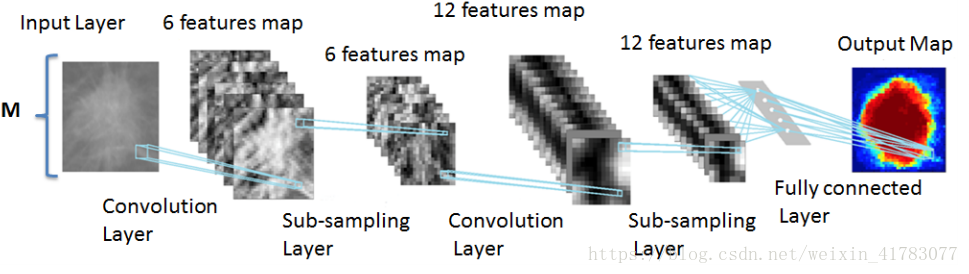

卷积神经网络是一个多层的神经网络,每层由多个二维平面组成,而每个平面由多个独立神经元组成。

图11 卷积神经网络的概念示范图

卷积神经网络的概念示范如图11所示。输入图像通过和三个可训练的滤波器和可加偏置进行卷积,卷积后在C1层产生三个特征映射图,然后特征映射图中每组的四个像素再进行求和,加权值,加偏置,通过一个Sigmoid函数得到三个S2层的特征映射图。这些映射图再进过滤波得到C3层。这个层级结构再和S2一样产生S4。最终,这些像素值被光栅化,并连接成一个向量输入到传统的神经网络,得到输出。

一般地,C层为特征提取层,每个神经元的输入与前一层的局部感受野相连,并提取该局部的特征,一旦该局部特征被提取后,它与其他特征间的位置关系也随之确定下来;S层是特征映射层,网络的每个计算层由多个特征映射组成,每个特征映射为一个平面,平面上所有神经元的权值相等。特征映射结构采用影响函数核小的sigmoid函数作为卷积网络的激活函数,使得特征映射具有位移不变性。

此外,由于一个映射面上的神经元共享权值,因而减少了网络自由参数的个数,降低了网络参数选择的复杂度。卷积神经网络中的每一个特征提取层(C-层)都紧跟着一个用来求局部平均与二次提取的计算层(S-层),这种特有的两次特征提取结构使网络在识别时对输入样本有较高的畸变容忍能力。